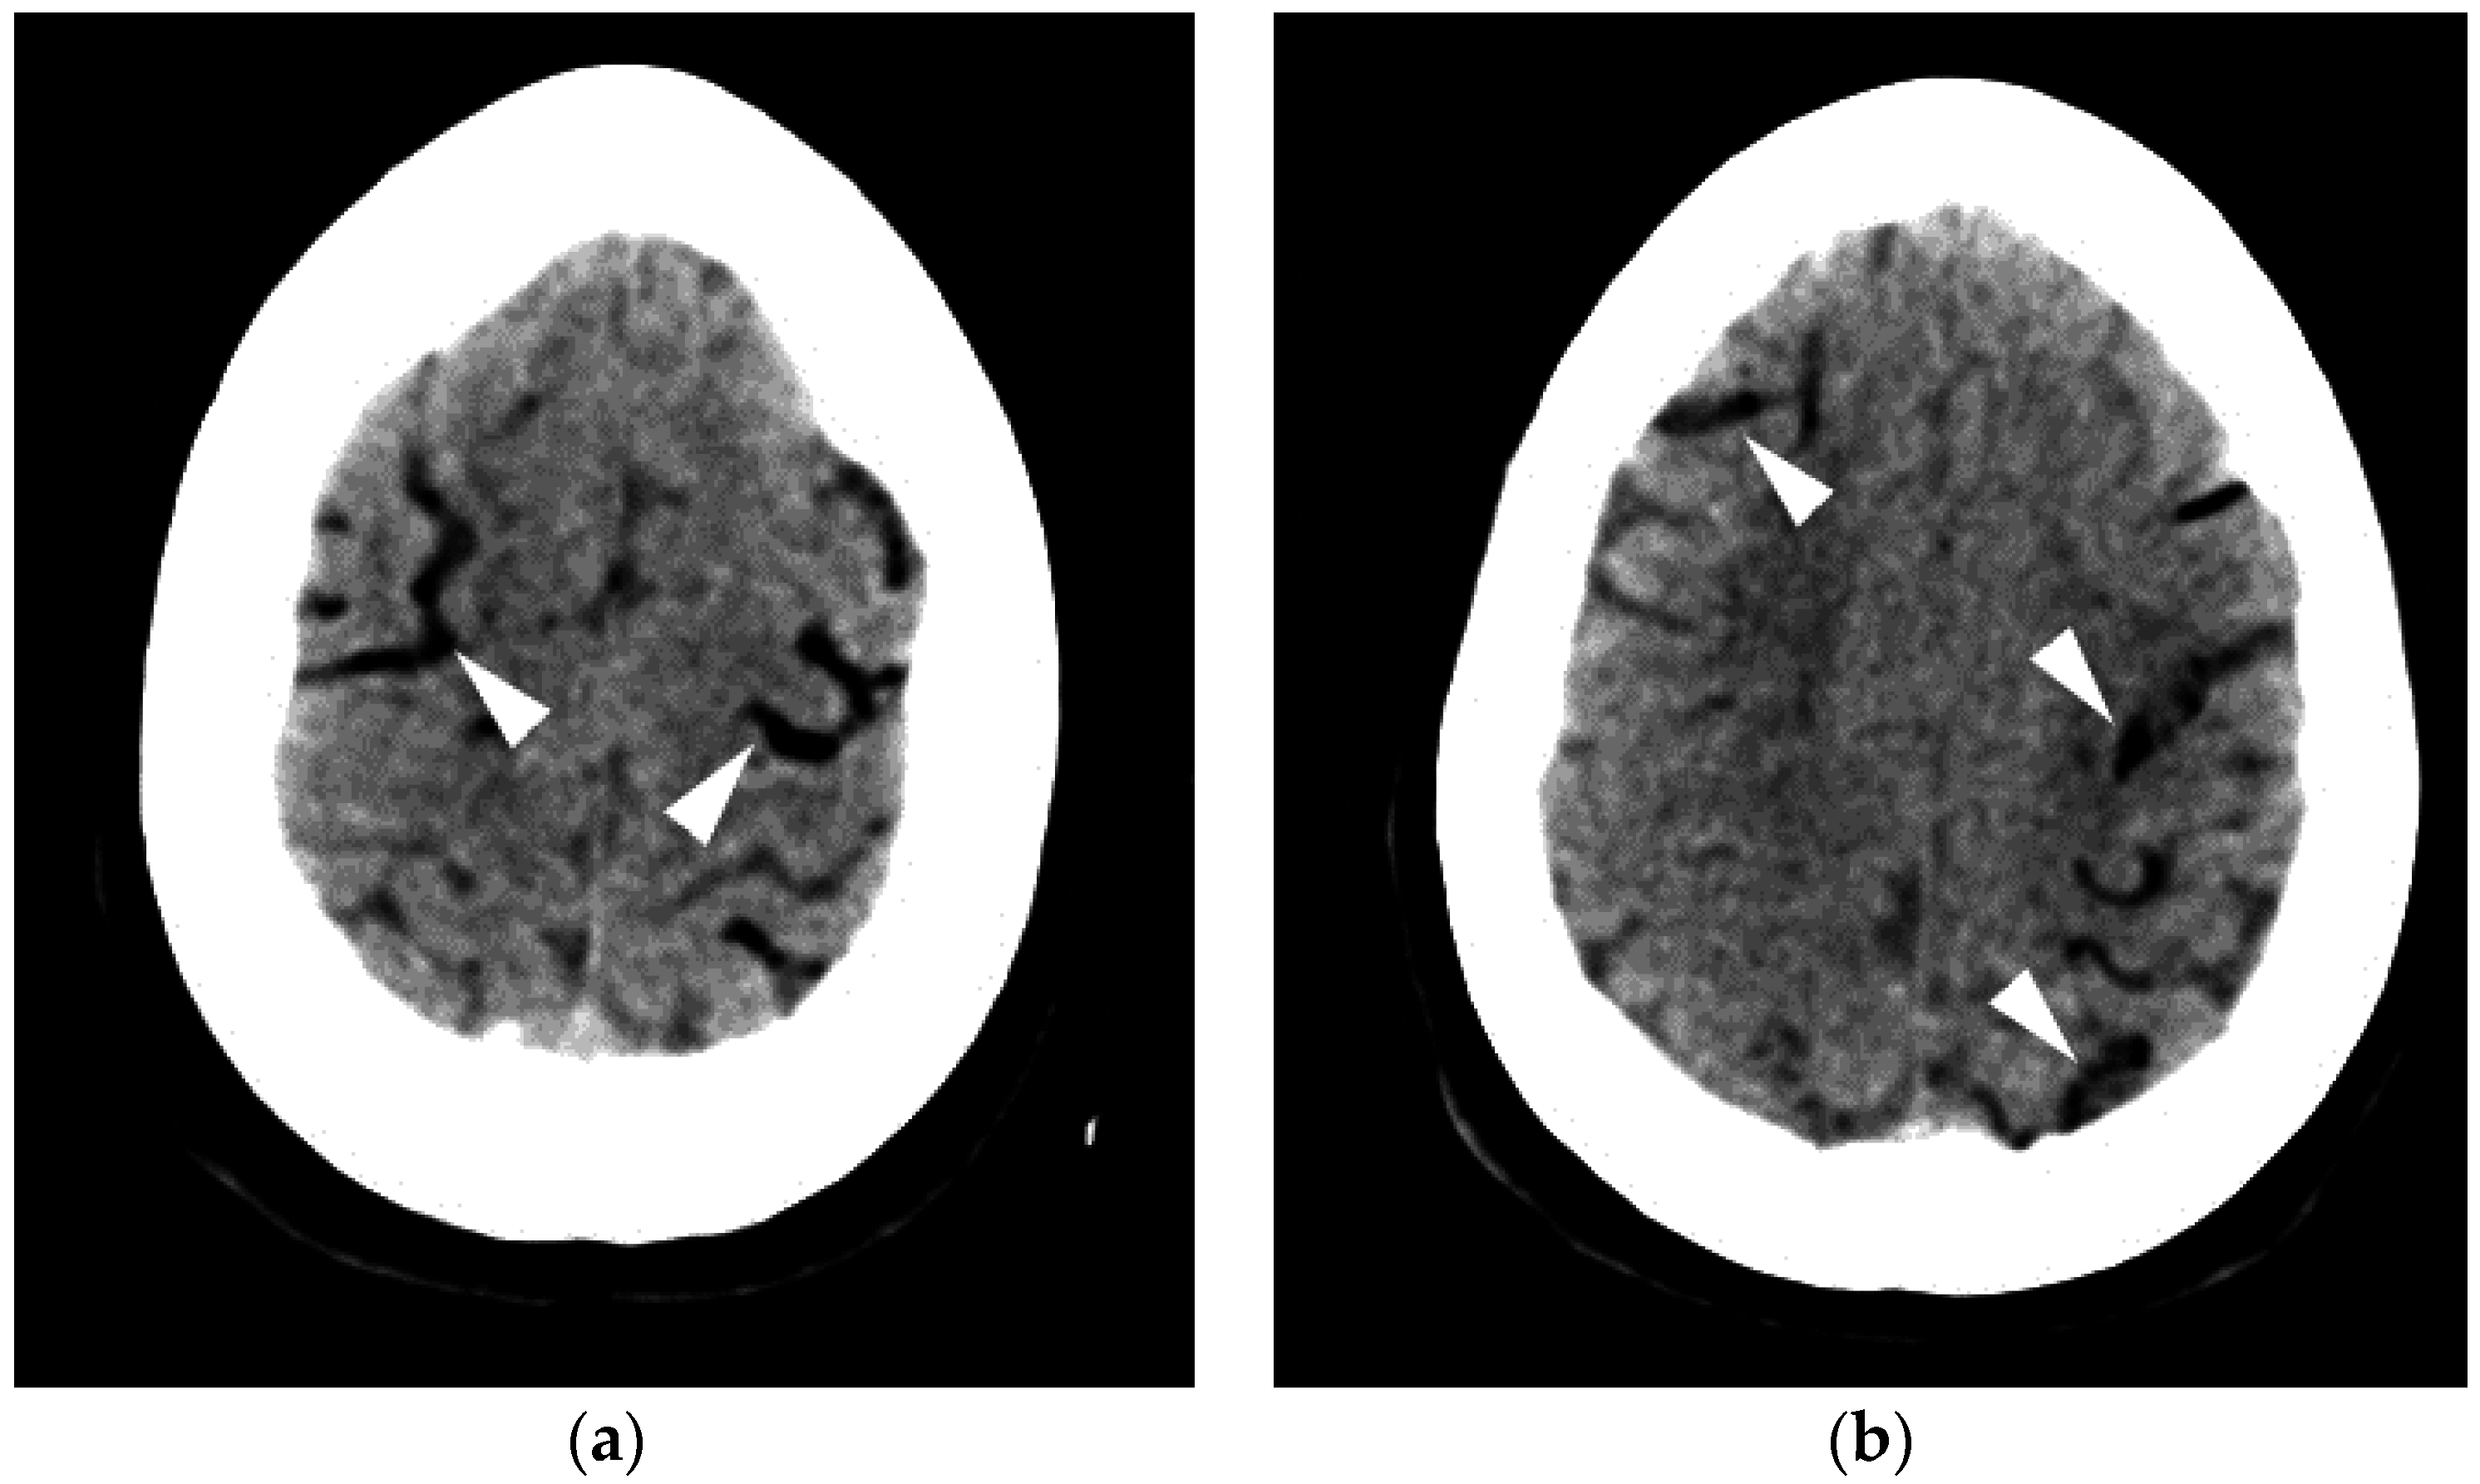

Written by roberta alexander — updated on april 1 pneumocephalus is the scientific name for the presence of air in the cranium.

You could see it if you. How 'air pockets' can form in your brain. Un blog che racconta di tutto a 360°. 18% off xiaomi mijia air purifier filter formaldehyde enhanced version s1 green for xiaomi mijia air purifier.